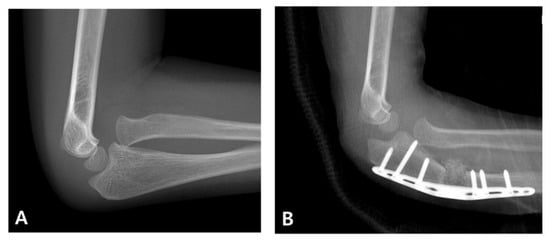

When diagnosis is delayed beyond the acute phase, the injury is considered a “neglected Monteggia fracture,” typically defined as untreated for more than two weeks. As illustrated in Figure 2, delayed treatment can result in chronic dislocation of the radial head, leading to progressive pain, valgus deformities, and a restricted range of motion [2,7]. Irreducibility due to soft tissue contracture or annular ligament entrapment may develop over time, and altered joint mechanics can result in degenerative changes and ulnar nerve dysfunction [2,8]. Surgical reconstruction (Figure 3), often involving ulnar osteotomy, open reduction, and annular ligament reconstruction, is necessary; however, the outcomes are generally inferior to those achieved with early intervention [2,9].

Figure 2. Radiographic presentation of a neglected pediatric Monteggia fracture. (A) Initial radiographs of a 4-year-old boy demonstrating a proximal ulnar fracture with anterior radial head dislocation. The injury was initially misdiagnosed as an isolated ulnar fracture, and the patient received conservative treatment at another institution. (B) Follow-up images taken after 6 weeks show fracture healing but persistent dislocation of the radial head, consistent with a neglected Monteggia fracture.